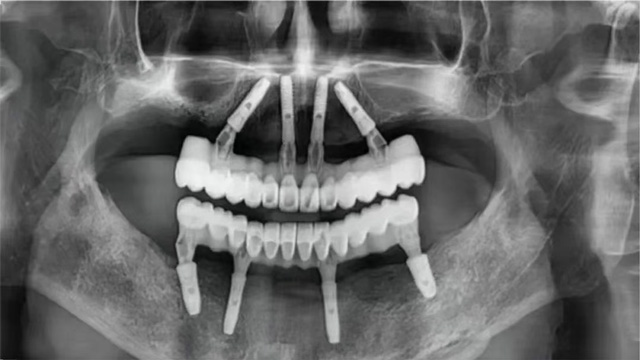

全口无牙颌即拔即种术后全景片

全口种植手术完成后,张先生感觉不错。稍事休息后完成了即刻修复,戴上了临时牙冠。几个月后,张先生回院复诊,戴上了正式牙冠。看着镜子里一排整齐又漂亮的牙齿,他露出了久违的笑容。

10年后,他庆幸自己选择了新桥口腔这样的医疗机构,庆幸遇到姜辰主任样有技术、有经验的医生,通过种植8颗种植体恢复了全口咀嚼功能,让他在晚年得以重拾口福。

张先生重获24颗牙